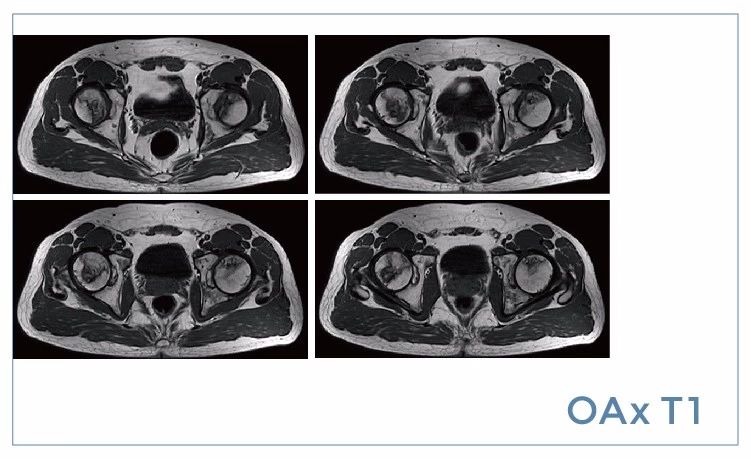

【朗润影像档案】20190719磁共振影像病例结果讨论

【朗润影像档案】磁共振影像病例分享(编号20190719)